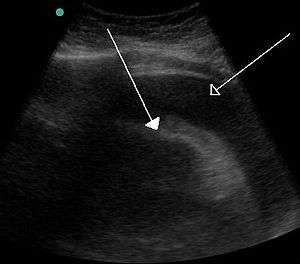

A very large hemorrhagic pericardial effusion due to malignancy as seen on ultrasound which was causing tamponade. closed arrow: the heart, open arrow: the effusion

There can, however, be disastrous consequences when tamponade occurs as a result of health problems, as in the case of cardiac tamponade. In this situation, fluid collects between the heart muscle and the pericardium. The pressure within the pericardium prevents the heart from expanding fully and filling the ventricles, with the result that a significantly reduced amount of blood circulates within the body. If left unchecked, this condition will result in death.